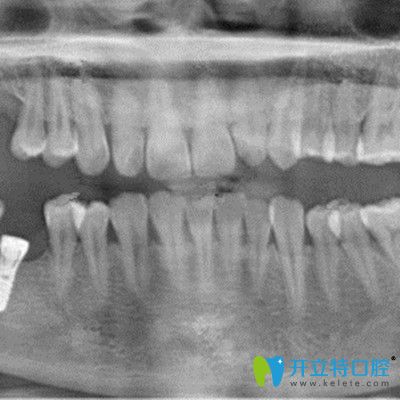

在吉林愛(ài)齒口腔做即刻種植牙拍片照片

再次到,譚醫(yī)生表示我的牙骨質(zhì)條件還是挺好的,當(dāng)天就做了手術(shù),裝入了種植體,戴了臨時(shí)冠,整個(gè)手術(shù)過(guò)程大概持續(xù)了一個(gè)小時(shí)左右。因?yàn)樽龅氖俏?chuàng)即可種植技術(shù),所以基本沒(méi)有痛感。